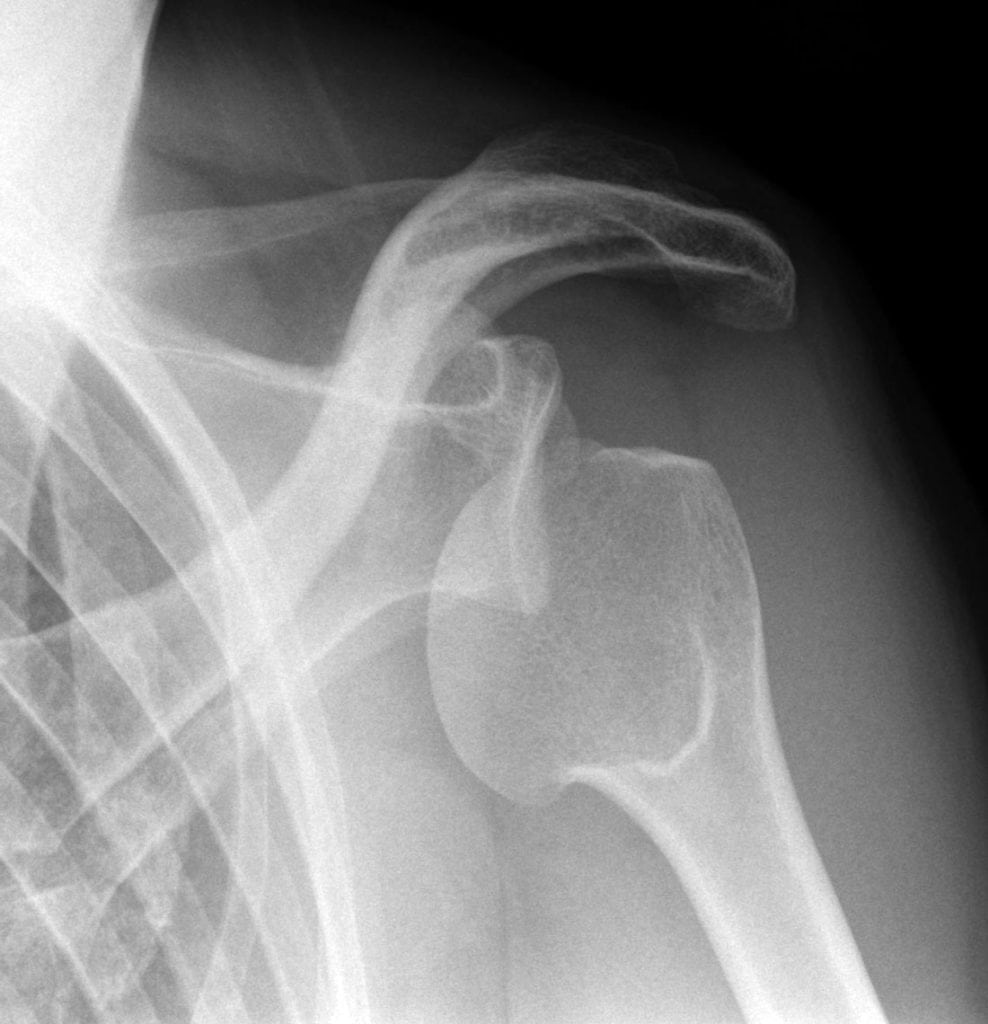

Для подтверждения диагноза проводится рентгенография, а при необходимости — МРТ. Терапия заключается в закрытом или открытом вправлении плечевого сустава, ношении повязки Дезо. На этапе реабилитации пациентам показаны физиопроцедуры, массаж, занятия лечебной физкультурой.

Довольно часто диагностируется сочетание вывиха с травмированием других суставных структур. Это перелом головки, отрыв одного из бугорков кости плеча, перелом впадины сочленения или отростков лопатки (акромиального, клювовидного).

| Формы вывиха плечевого сустава | Характеристика повреждения |

| Передний | Диагностируется в 95% случаев всех вывихов плеча. Плечевая кость смещается кпереди в нижнюю часть клювовидного отростка. Ее головка полностью утрачивает контакт с лопаткой. К вывиху такого вида приводит непрямое травмирование руки, которая в момент повреждения находится в разогнутом положении. Переднее смещение кости провоцирует также прямое механическое воздействие на нее, например, сильный удар сзади |

| Задний | Головка плечевой кости смещается кзади в результате механического воздействия на переднюю область сочленения. В редких случаях задний вывих происходит из-за удара в места, расположенные поблизости плеча — предплечье, локоть, кисть. К заднему смещению костной головки приводит удар в сустав, находящийся в согнутом положении при его вращении |

| Нижний | Самой редкой считается форма вывиха, при которой костная головка смещается вниз относительно лопатки. Сустав травмируется вследствие механического воздействия в положении отведения, например, при поднятии руки вверх. Итогом становится смещение плечевой кости под впадину сочленения с фиксацией конечности в патологической позиции — поднятой над головой. Нередко при нижнем вывихе повреждаются нервы и сосуды, локализованные в подмышечной впадине |